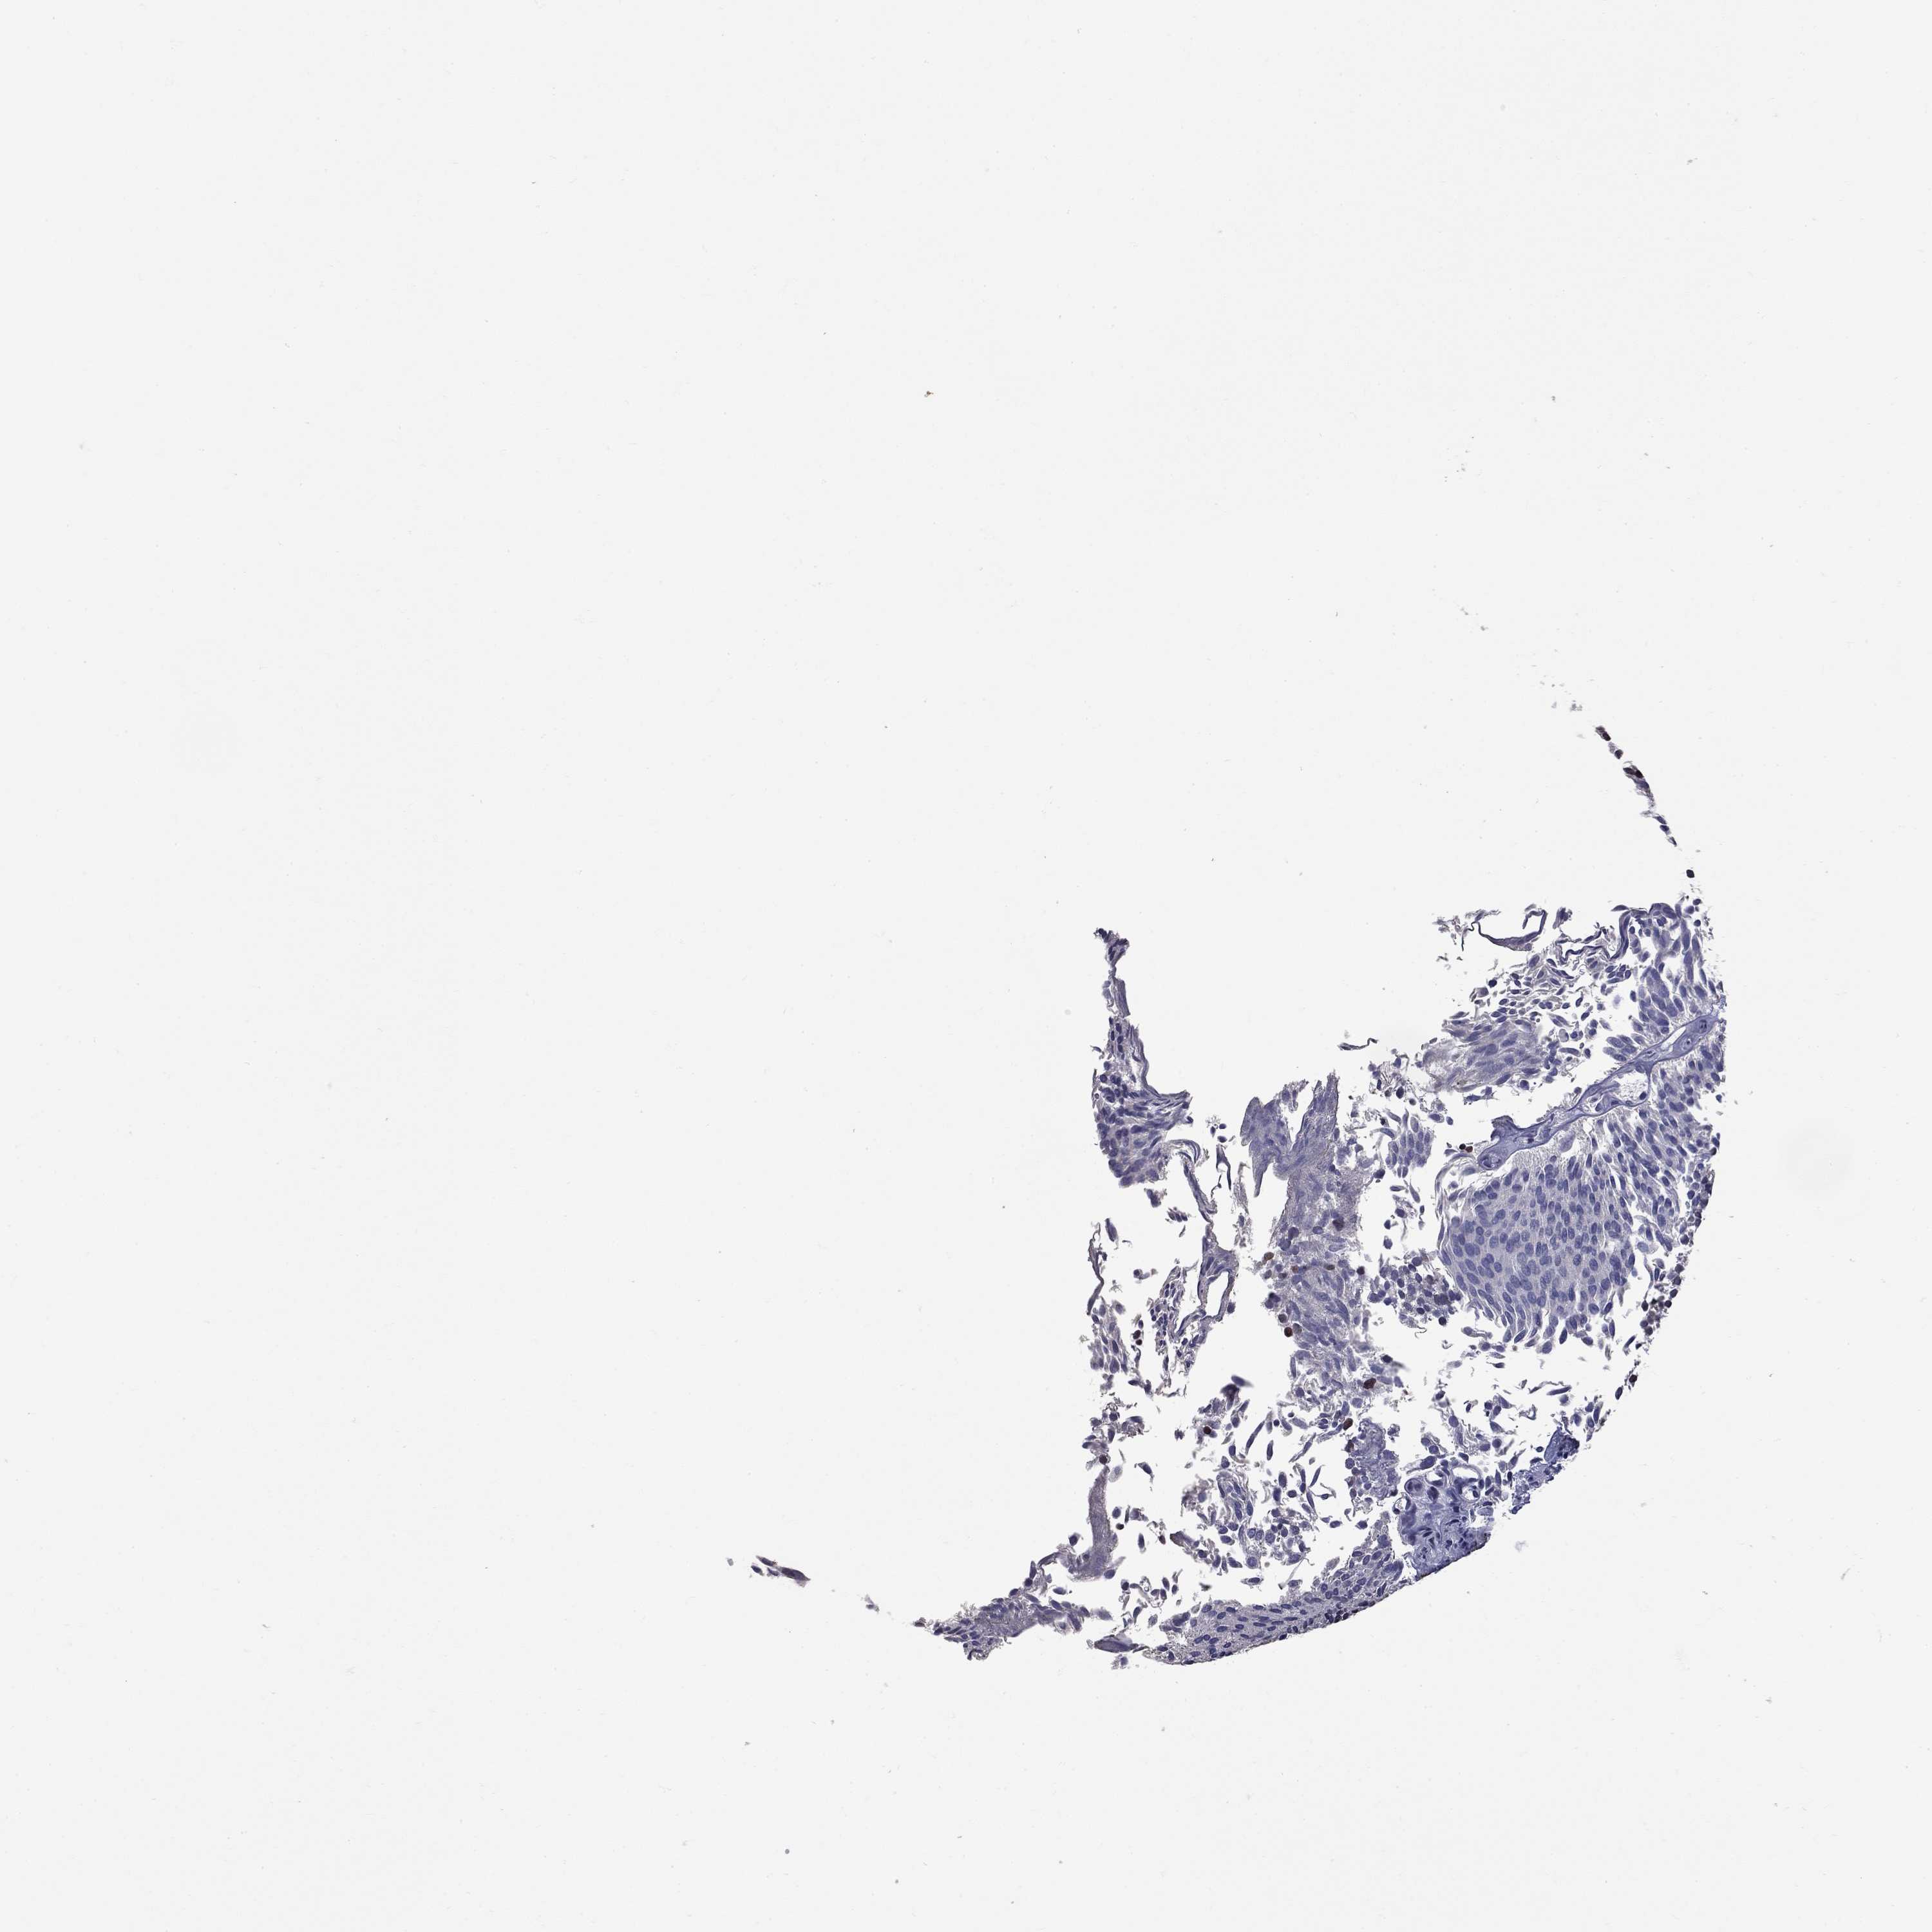

UROTHELIAL CANCER - Protein expressioni

A mouse-over function shows sample information and annotation data. Click on an image to view it in a full screen mode. Samples can be filtered based on level of antibody staining by selecting one or several of the following categories: high, medium, low and not detected. The assay and annotation is described here.

Antibody stainingi

Antibody staining in the annotated cell types in the current human tissue is reported as not detected, low, medium, or high, based on conventional immunohistochemistry profiling in selected tissues. This score is based on the combination of the staining intensity and fraction of stained cells.

Each image is clickable and will lead to virtual microscopy that enables deeper exploration of all samples and also displays staining intensity scores, fraction scores and subcellular localization as well as patient and tissue information for each sample.

Antibody HPA076284

Staining

High

Medium

Low

Not detected

Intensity

Strong

Moderate

Weak

Negative

Quantity

>75%

75%-25%

<25%

None

Location

Nuclear

Cytoplasmic/membranous

Cytoplasmic/membranous,nuclear

Urothelial carcinoma, High grade

Urothelial carcinoma, Low grade